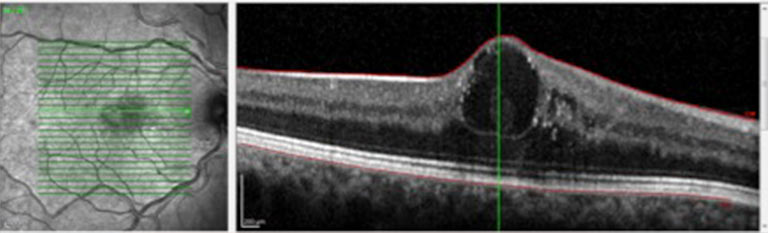

Existen muchas enfermedades de la mácula que pueden manifestarse en diferentes momentos de la vida. Si bien no todas tienen un tratamiento específico, surgirá del correcto diagnóstico la posibilidad terapeútica de cada una.